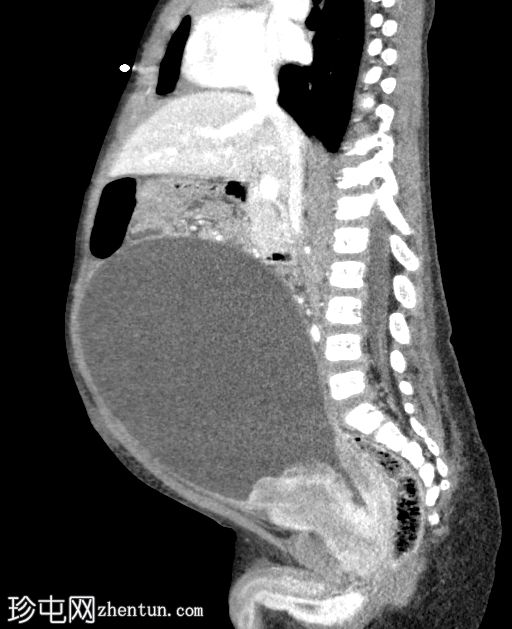

矢状位增强扫描(门静脉期)

膀胱颈下部可见一异质性强化软组织肿块,导致膀胱出口梗阻和膀胱明显囊性扩张(头尾长:19厘米)。

肿块前方与耻骨联合相邻,位于Retzius间隙内;后方与直肠和乙状结肠相邻;虽然脂肪间隙模糊,但未见明确的侵犯。

双侧输尿管肾积水,继发于膀胱出口梗阻。